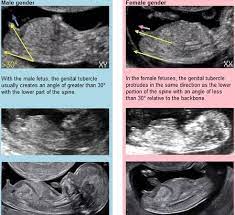

Schedule an appointment to see your doctor The baby's genes determine sex. But take it from us — it's just a prediction, and things might change! Can you tell gender at 10 weeks? Private parts nub pointing up less than 30 percent = girl.

While the purpose of the imaging is to check for the proper development of the fetus, this ultrasound also has the ability to reveal the gender of your baby. Facebook youtube instagram twitter pinterest. Amniocentesis is an invasive test used to determine if there are any possible genetic abnormalities. Private parts nub pointing up less than 30 percent = girl. But developments in noninvasive prenatal tests (nipts) mean you can be let in on this little secret with a simple blood test — even if gender determination isn't their main purpose — as early as 10.

Not sure why they say you find out earlier maybe because you usually get to see them lots more. We had names picked out and everything. But since all of their anatomical development isn't complete until around 18 to 20 weeks, that's usually when the anatomy scan is performed. Can you tell gender at 10 weeks? Facebook youtube instagram twitter pinterest. An ultrasound when you are between 15 and 22 weeks pregnant can also enable the technician or physician to identify your baby's gender, because at this stage of pregnancy a number of signs may show clearly on the scan. The opening just under the tail is the anus. We were 15w6d, confirmed at our anatomy scan during week 20. But developments in noninvasive prenatal tests (nipts) mean you can be let in on this little secret with a simple blood test — even if gender determination isn't their main purpose — as early as 10. Can you tell gender at 12 weeks? The baby's genes determine sex. Also have it confirmed a couple times because sometimes they can be wrong. Nipt is the earliest option available to finding out the gender of your baby as this can be done from 9 weeks on wards.